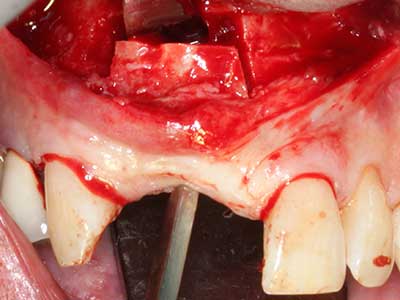

Bone tissue is not simply a mineral structure but also contains a substantial proportion of collagen fibres. This means it not only has good compressive strength but also a degree of flexibility, which can be taken advantage of when performing bone augmentations. In the classical expansion procedure using bone splitting, the atrophied alveolar ridge is split longitudinally and carefully expanded after reaching an adequate osteotomy depth (Fig. 13-16), ideally without substantial removal of the periosteum (Brugnami, Caiazzo et al. 2014, Stricker, Fleiner et al. 2014). Screw and plate systems with increasing expansion distance have proven effective in separating the two bone lamellae while remaining below the fracture threshold. In general, residual bone widths of at least 3–4 mm are required (Chiapasco, Zaniboni et al. 2006) to guarantee adequate flexibility and sufficient bone coverage of the future implants. If necessary, a vertical relief osteotomy on one or both sides can improve flexibility. A combination with additional augmentation techniques, particularly on the buccal side, has been described as an alternative to the classical technique.